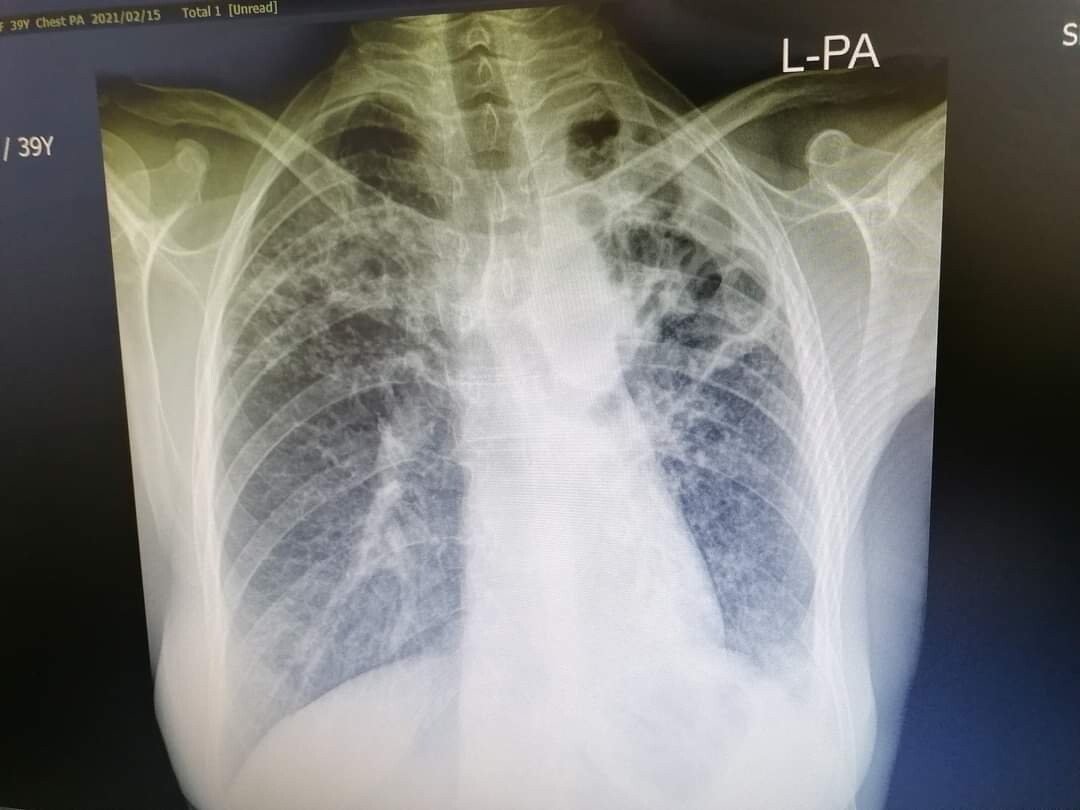

Tuberculoza este una dintre primele 10 cauze de deces la nivel mondial, fiind o boală cauzată de germeni care se transmit de la o persoană la alta prin aer. Tuberculoza afectează de obicei plămânii, dar poate afecta și alte părți ale corpului, cum ar fi creierul, rinichii sau coloana vertebrală. Boala se transmite pe cale aeriană, prin inhalarea microbilor răspândiți în atmosferă de către bolnav atunci când tușește, râde, strănută, vorbește, cântă sau expectorează, răspândind în jur particule de salivă. Factorii de risc pentru tuberculoză sunt: fumatul, stresul, un sistem imunitar slăbit, condiții de trai insalubre, lipsa unui adăpost, încarcerarea.